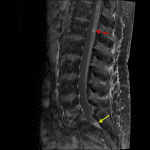

- Multifocal nodular enhancement along nerve roots of the cauda equina with enhancing material layering in the caudal thecal sac at the level of S2

- Thin linear enhancement along the surface of the conus and visualized lower thoracic spinal cord

- Leptomeningeal metastatic disease

Multifocal nodular enhancement along nerve roots of the cauda equina with enhancing material layering in the caudal thecal sac at the level of S2 and thin linear enhancement along the surface of the conus and visualized lower thoracic spinal cord, concerning for extensive leptomeningeal metastatic disease.